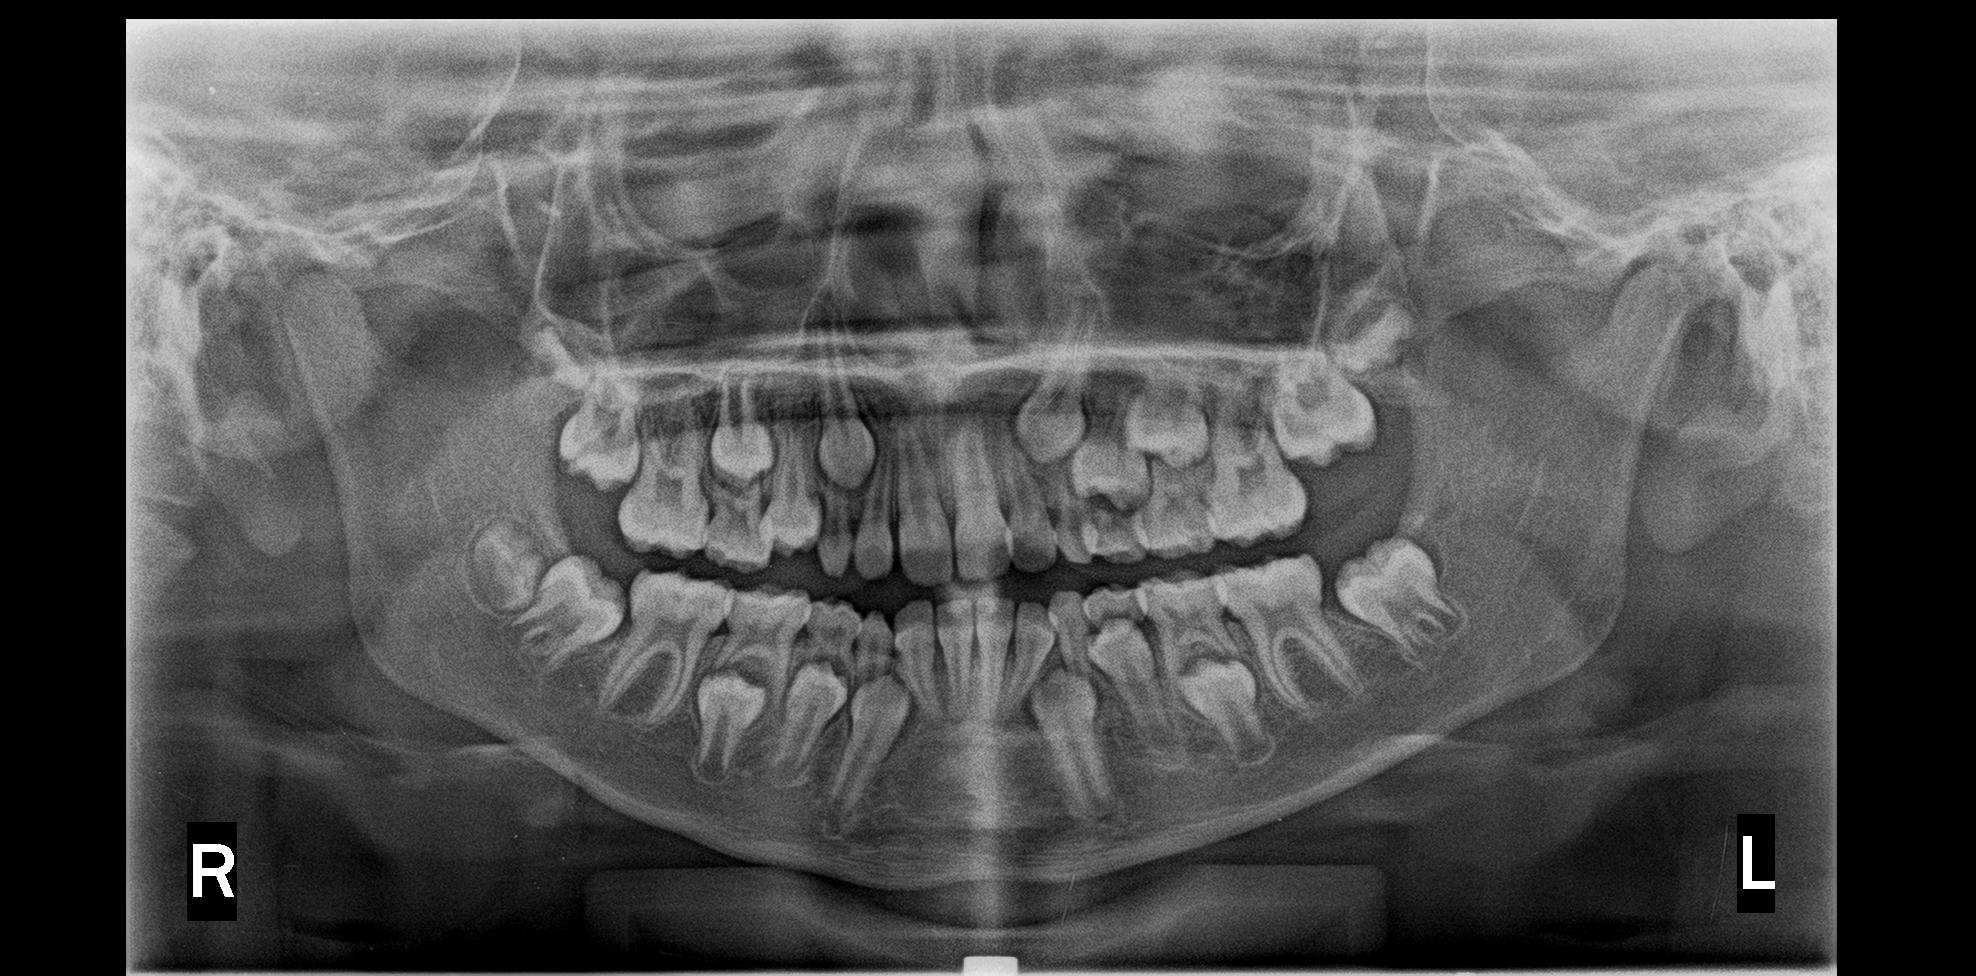

Las anomalías dentales son un grupo de alteraciones morfológicas, que se pueden expresar en la corona o en la raíz dental; aparecen durante el desarrollo de los órganos dentales, se ha establecido que tienen un componente genético y molecular importante. También se han planteado influencias medioambientales, traumáticas y microbiológicas. Las anomalías morfológicas dentarias son comunes, y se presentan con una incidencia de 74,7% según Freer (1998). Los dientes cónicos, en clavija o reducidos tienen una incidencia menor y muestran mayor incidencia en dentición permanente, así como en los incisivos laterales superiores. El mencionado defecto va a ser origen de alteraciones en la oclusión, la longitud de arco, compromisos estéticos que van a afectar la autoestima del paciente. El propósito de este trabajo es presentar dos casos de dientes cónicos, uno en dentición permanente, otro en dentición temporal relacionándolos con el marco teórico encontrado en la literatura sobre las influencias genéticas que juegan un papel importante en la aparición de la mencionada anomalía, aunque no se pudo realizar el estudio genético que se quisiera a causa limitaciones económicas.